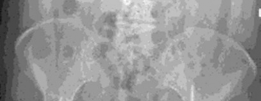

A 20-year-old man is brought to the emergency department following a high-speed road traffic accident in whic…